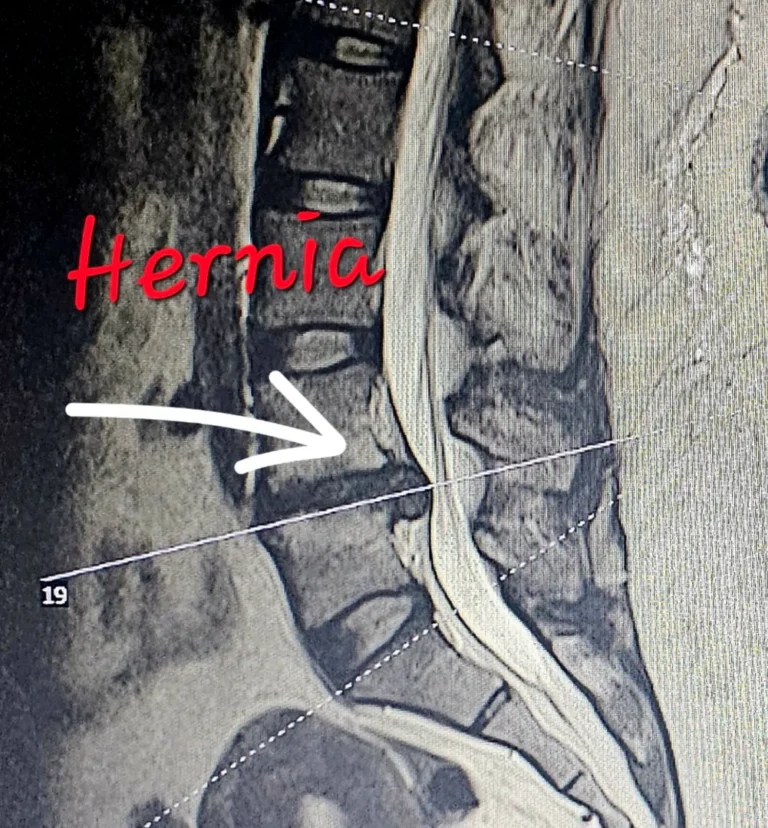

Specialist in the diagnosis and surgical management of conditions of the nervous system, with expertise in minimally invasive spine surgery, skull base procedures, neuro-oncology, and complex cranial and spinal pathologies.

- ✔ Minimally Invasive Spine Surgery

- ✔️ Minimally invasive spine surgery

- ✔️ AO Spine Trauma and Spine Courses

- ✔️ Comprehensive Spine Program – Zimmer Biomet (Miami)

- ✔️ Vertebral Stentoplasty for Osteoporotic Fractures – Case Report and Review